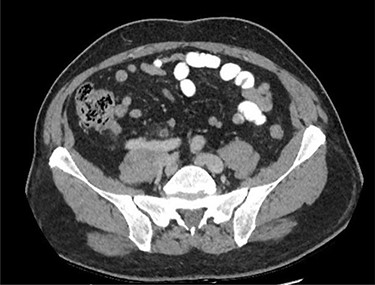

This collection was drained under ultrasound guidance, and a pigtail catheter was left in situ for 1 week. The patient progressively recovered. A repeat CT of the abdomen and pelvis after a week demonstrated a reduction of the collection (Fig. 3).

CT of the abdomen and pelvis demonstrating a reduction in size of the fluid collection/abscess in the inguinal hernia sac in (A) coronal (B) sagittal and (C) apical planes.